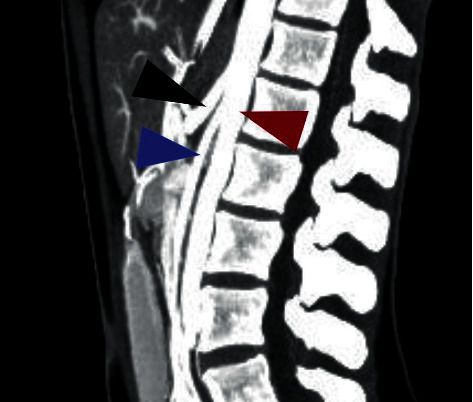

Superior mesenteric artery (SMA) syndrome is a rare etiology of upper gastrointestinal obstruction. The measured angle between the SMA and the aorta is typically between 38 and 65° and maintained by mesenteric fat. Excessive fat loss can lead to intestinal obstruction due to an exaggerated acute angularity of the SMA, compressing the third part of the duodenum. We present a 22-year-old female with a history of aplastic anemia, status post bone-marrow transplant, who presented with intractable nausea and had confirmed SMA syndrome on CT angiography. Subsequently, the patient underwent nasogastric decompression and successful laparoscopic duodenojejunostomy.

摘要肠系膜上动脉症候群是一种罕见的上消化道梗阻病因。SMA与主动脉之间的测量角度通常在38°至65°之间,由肠系膜脂肪维持。由于SMA的急性角度过大,压迫十二指肠的第三部分,脂肪的过度减少可导致肠梗阻。我们报告一位22岁的女性,有再生障碍性贫血史,骨髓移植后的状态,她表现为顽固性恶心,CT血管造影证实为SMA综合征。随后,患者接受了鼻胃减压术和成功的腹腔镜十二指肠空肠吻合术。